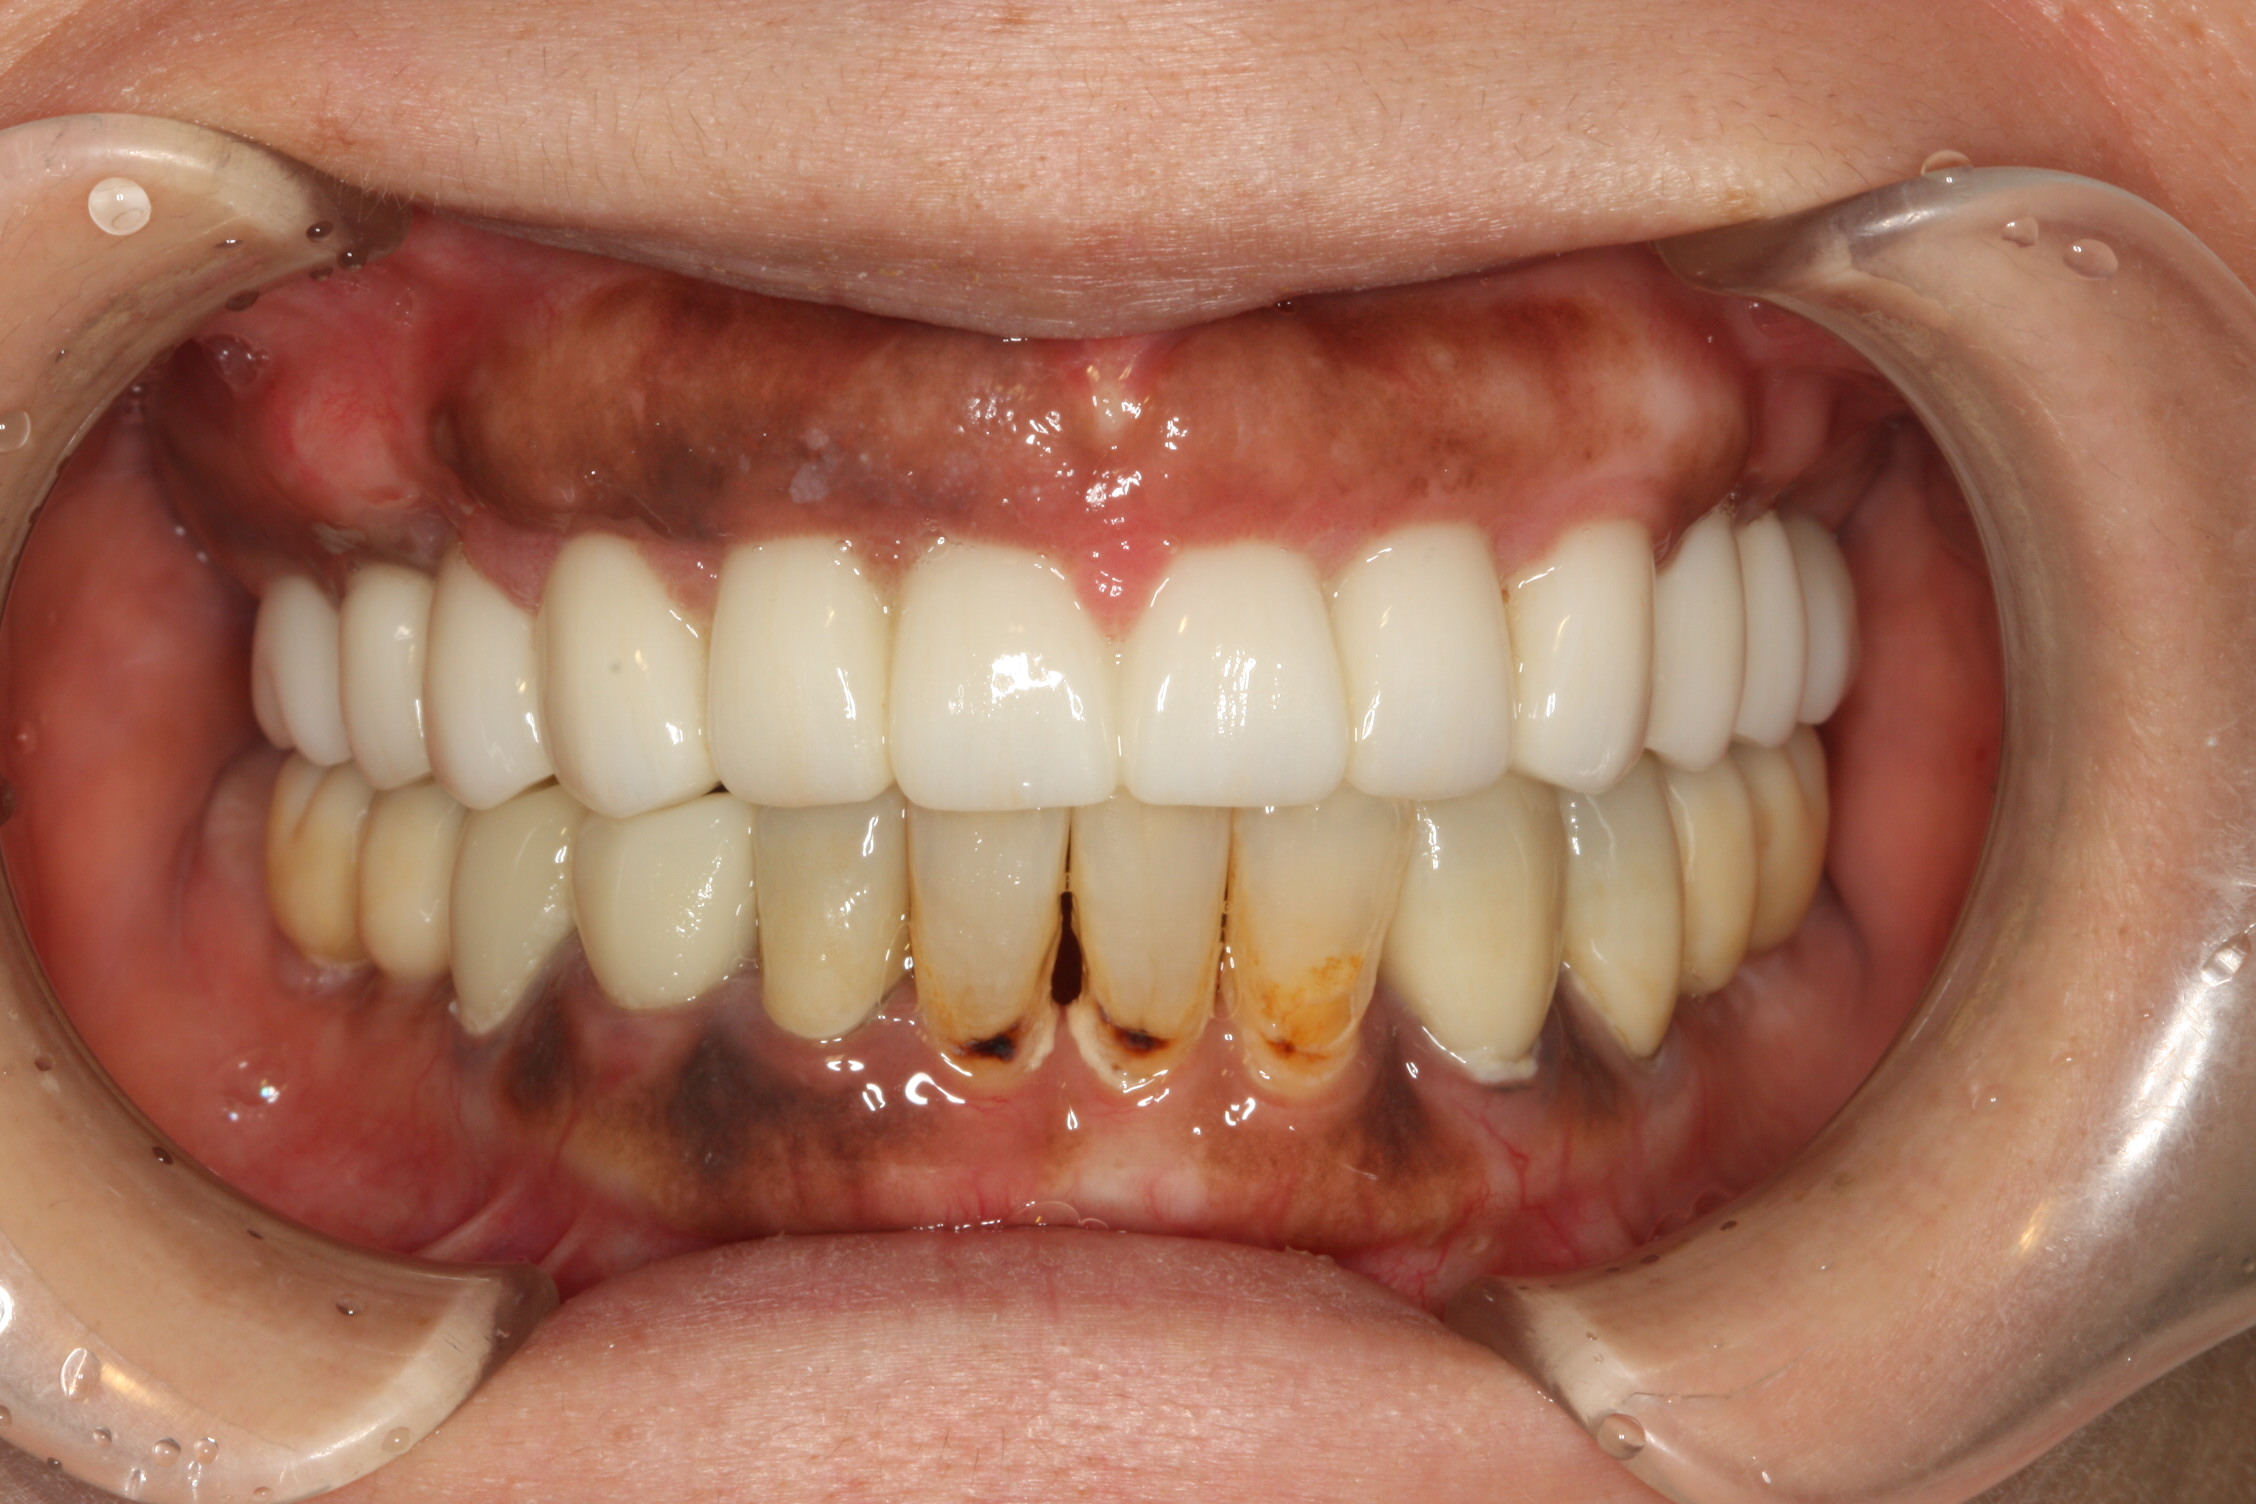

case.1

Before

After

| 概要 | 上顎の残存している歯は虫歯が深いので全て抜歯し、前歯は歯肉のラインが変化しないように歯根の外側を一部残してインプラントを埋入します。奥歯は上顎洞底まで距離がないのでソケットリフトをしてインプラントを埋入します。 |

|---|---|

| 主訴 | 前歯に歯を入れて審美を回復したい。奥歯で食事ができるようにしたい。 |

| 治療期間 | 1年 |

| 治療回数 | 15回 |

| 治療費 | 320万円 |

| 治療内容 | 上顎に6本のインプラントを埋入してボーンアンカードブリッジで補綴 |

| 治療のリスク | 1次手術後は副鼻腔を刺激しないように、鼻をかんだりしないことが大切です。 |

※表示金額は全て税込です。